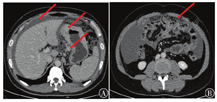

实验室检查:CA-724为300 U/ml,CA-125为481.6 U/ml;腹腔积液脱落细胞检查找到腺癌细胞。临床诊断:胃癌,腹腔转移。诊疗过程:给予全身化疗联合腹腔热灌注治疗。转化治疗方案:化疗第1天依据患者体表面积给予奥沙利铂(80 mg/m2),静脉滴注2 h;化疗第1~14天,口服替吉奥胶囊,60 mg/次,2次/d;化疗第3天给予顺铂腹腔热灌注治疗,顺铂50 mg/m2,加入0.9%氯化钠溶液2 000 ml,灌注速度35~45 ml/min,水温控制在41 ℃左右,灌注45~60 min。3个疗程后依据实体肿瘤评价标准进行影像学评估:患者ycTNM分期为T3N0-1M0,肿瘤缩小,淋巴结缩小,肿大淋巴结数量减少,腹腔积液消失,疗效评价为部分缓解(图2)。肿瘤标志物:CA-724为2.63 U/ml,CA-125为7.06 U/ml。化疗毒性反应:0级。进一步行腹腔镜探查术,术中见腹膜纤维化改变,未见腹腔转移(图3)。遂行根治性全胃切除术(图4、图5)。术后病理①低分化腺癌;②Lauren分型:弥漫性;③脉管浸润:+;④神经浸润:-;⑤淋巴结:0/30;⑥ypTNM:T3N0M0(图6)。患者术后恢复良好,术后第7天顺利出院。术后第3周开始进行了4个疗程SOX化疗(奥沙利铂+替吉奥)。随访1年,未见肿瘤复发。

注:图A箭头处为脾动脉及脾静脉;图B箭头处为肝总动脉及门静脉